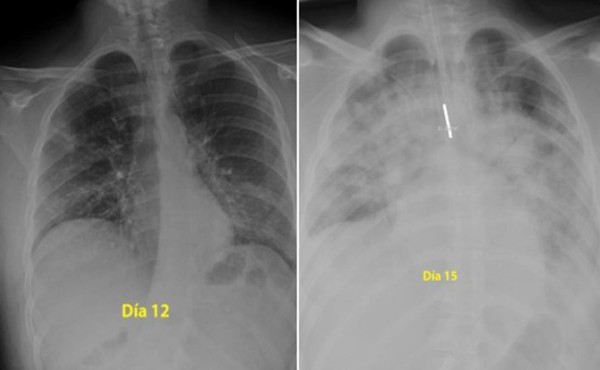

Un tuit que muestra la comparación de dos radiografías de tórax supuestamente afectado por una neumonía provocada por el nuevo coronavirus ha sido compartido más de 70.000 veces en distintas redes sociales.

El mensaje asegura que las imágenes son de un paciente infectado de 28 años. Médicos especialistas consultados por AFP Factual señalaron que las imágenes son compatibles con la evolución de la neumonía en un paciente con COVID-19 de esa edad.

“Para los que se creen inmortales y siguen saliendo al parque sin hacer caso a la orden de permanecer en domicilio, estas son las radiografías de un chico de 28 años intubado en la UCI en mi hospital por #coronavirus. Pista: los pulmones es lo negro, lo blanco es neumonía”, dice el tuit del 15 de marzo pasado, fecha desde la cual se ha retuiteado más de 70.000 veces.

* Gemma Solana, del departamento de radiología torácica del Hospital Universitario Mútua de Terrassa (Barcelona), aseguró: “Desde hace una semana tenemos muchos casos de contagiados por COVID-19 con el primer tipo de placa, y vemos que los casos progresan. En el hospital estamos viendo que una evolución como la que muestran las imágenes [NDLR: de tres días] puede darse incluso en horas, por lo que las imágenes son compatibles con ese tiempo de evolución”.

“También hay que tener en cuenta que, sobre todo, hacemos radiografías a los casos más complicados, y que no todos los afectados por la enfermedad presentan estas afectaciones”, añade.

Solana también afirma que el cuadro médico podría ser compatible con un paciente de 28 años, tal y como afirma la publicación viral: “No se puede determinar, pero el corazón que se ve en las placas es pequeño, puede ser de una persona joven”.

* Por su parte, Miguel Ángel de la Cámara, técnico especialista en radiodiagnóstico del Hospital Siberia Serena de Badajoz y colaborador del portal español Salud sin bulos, señaló también vía telefónica: “Las imágenes muestran un caso de neumonía que se puede dar tanto con coronavirus como sin él. Ese tipo de evolución en positivos de COVID-19 se está dando en casos de mayor edad, pero tampoco podemos descartar que se trate de un paciente joven, que pueda tener una mayor susceptibilidad”.

En conclusión, las imágenes difundidas son compatibles con una rápida evolución de una neumonía provocada por COVID-19 en un paciente joven, según confirman cuatro expertos médicos en la materia.